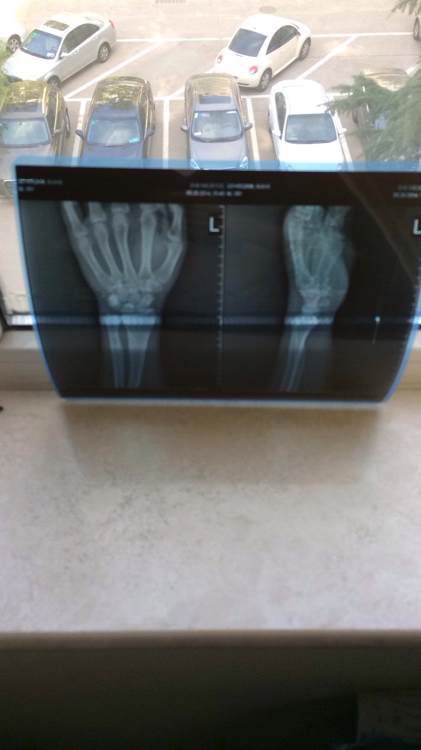

摔掉了一架顶级车的钱、要手术、多的不说、只求安慰!

回复 宿舍寮长 :我是错位加骨折、必须手术

半年不能摸车